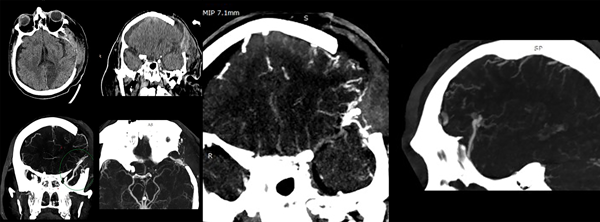

A las 72 horas postoperatorias y con el paciente estable hemodinámicamente, se reconsidera el hallazgo intraoperatorio de los vasos corticales anómalos junto con lo llamativo del volumen del hematoma y se presume un posible sangrado espontáneo. Se decide realizar imagen de control que incluya estudio de los vasos intracraneanos (a tales fines en nuestra institución solo se cuenta con la posibilidad de realizar AngioTC, Fig. 2).

Figura 2. TC y AngioTC a las 72 horas de evacuación del hematoma.

La AngioTC revela craniectomía extensa, retorno a la línea media de estructuras centrales, una nueva área hipodensa que corresponde al territorio vascular de la arteria cerebral posterior izquierda, higroma hemisférico derecho laminar y un hallazgo vascular a nivel del extremo superficial de la cisura silviana, que se observa como un vaso de gran calibre en tiempo venoso del contraste, con un trayecto proximal que termina en contacto con ramas de M3 y un trayecto distal voluminoso que se dirige hacia el polo temporal y se pierde en la base del mismo a nivel del tercio medio de esa misma fosa temporal.

Con los datos obtenidos de este estudio se diagnostica fístula arteriovenosa cerebral, identificando su afluente principal en la cara profunda y superior del trayecto varicoso central, proviniendo aparentemente de ramas de M3 en la profundidad de la cisura silviana. El trayecto varicoso central se extiende sobre la superficie de la cisura homónima y se dirige al polo temporal sin aparente comunicación a los senos durales normales. Se grafican imágenes clave en la Figura 3.

Figura 3. Gráfica de la interpretación de la lesión vascular. En la última imagen de reconstrucción 3D se puede observar la disposición de la várice venosa central que se continúa con un tramo intradural de trayecto sui generis (verde).